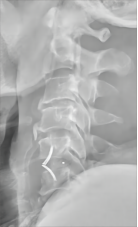

颈椎前路减压融合术适用于①屈曲型颈椎骨折或骨折脱位所致的颈椎创伤性不稳定;②颈椎爆裂性骨折,椎体粉碎,压迫脊髓或脊髓前动脉,产生脊髓前综合征,需做前路减压,解除脊髓受压。③后路广泛性椎板切除,颈椎不稳,经后外侧融合仍不牢固。目前我科已成功开展前路ACDF技术、ACCF技术、ROI-C插片技术、Zero-P零切迹技术,具有创伤小、恢复快、疗效佳,早期下床活动的优点。